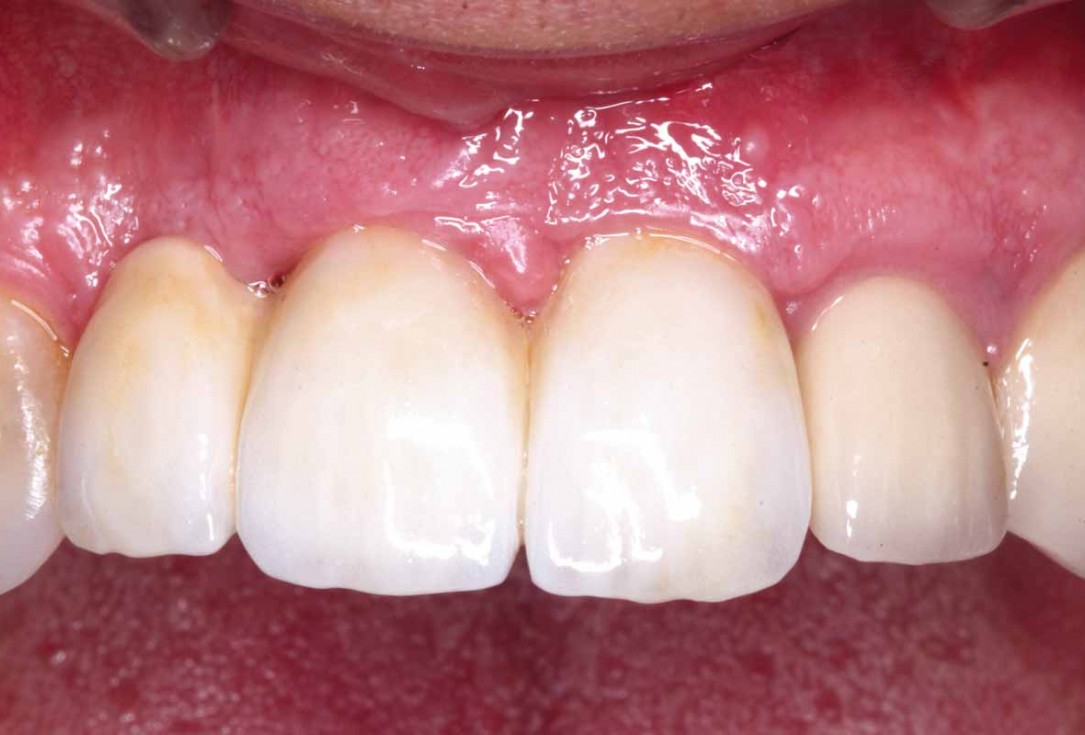

26/27 - Final screw retained restoration 5 months after surgery

GBR and soft tissue augmentation with cerabone® and mucoderm® - H. Maghaireh & V. Ivancheva